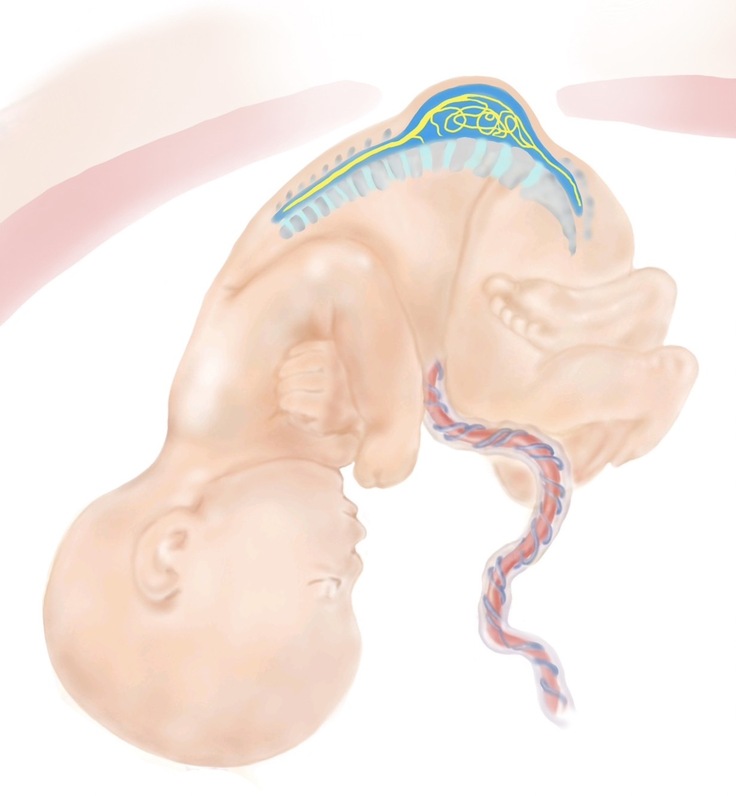

みなさん、お気づきだと思いますが、このプロジェクトの紹介ページには、たくさんのイラストを載せています。お腹の中で病気になっている赤ちゃんの絵なので、見る人に不安やこわさを与えないように、やさしいタッチで描いたイラストを掲載しています。

実は、このイラスト、私たちの仲間で、大阪大学の総合周産期母子医療センターで事務職員として働いているKさんが描いてくれたものなんです。見ていると穏やかになる落ち着いた絵ですよね。しかも、病気のことをできるだけ正確に表現したいので、一度描いてくれた絵を私たちと何度も見直して、正確に表現できるようになるまで根気強く描き直してくれてできたイラストたちなんです。大変思い入れのあるイラストたちです。

この場を借りて、Kさん、ありがとう。これからもよろしくお願いします。